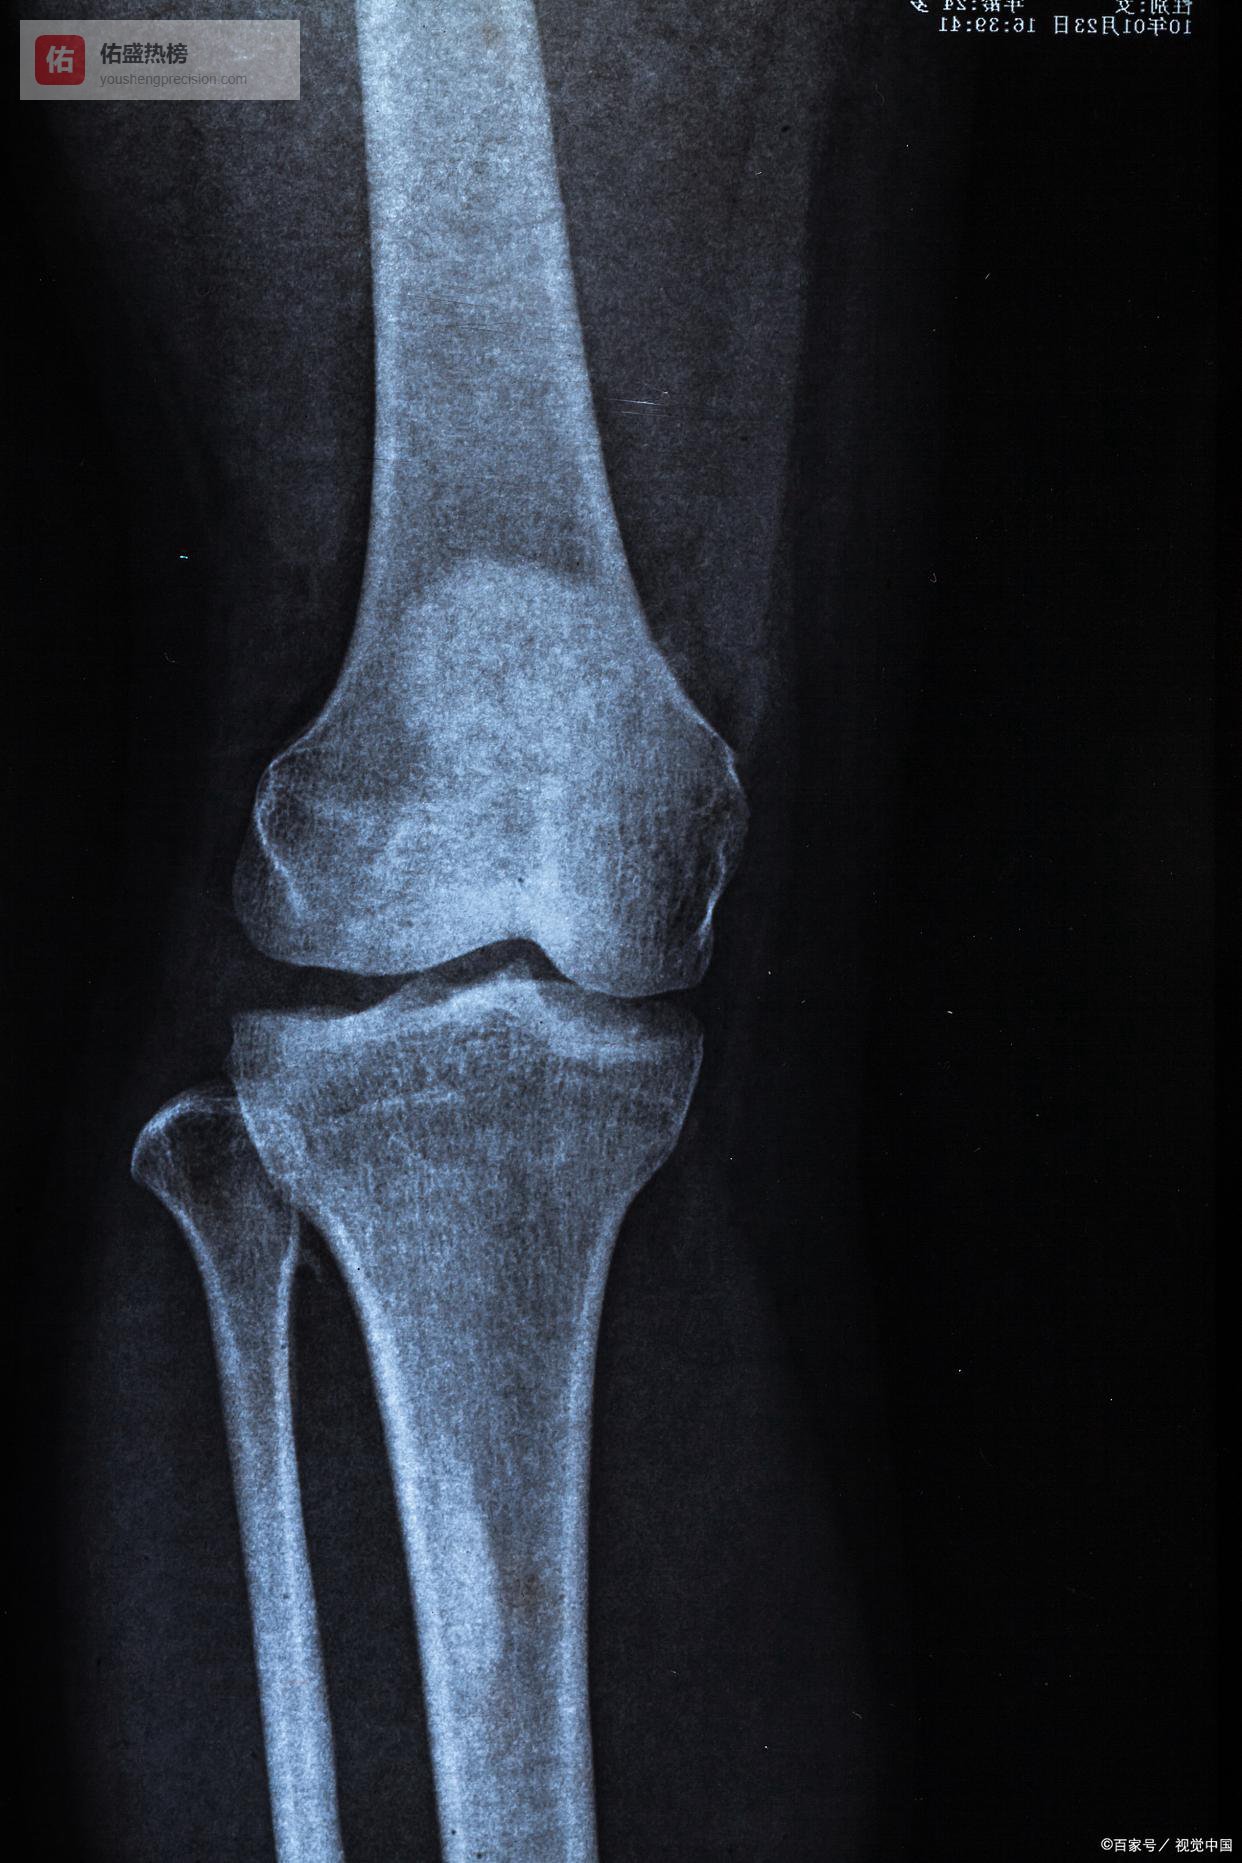

### 一、体重与关节压力关联研究1. 核心研究(髋关节聚焦):相关临床研究证实,**体重每增加1公斤,行走时髋关节压力增加3-5倍**,长期超负荷会导致股骨头微损伤、软骨加速磨损,BMI≥30的人群,髋关节骨关节炎发病率升高2-3倍,脂肪组织释放的促炎因子会加剧这一过程。2. 延伸研究(关节负荷通用):北京市卫生健康委员会相关研究显示,站立时膝关节承受体重1-2倍压力,上下楼梯时达3-4倍,肥胖者患膝关节炎的风险是正常体重者的4-7倍,减重5%-10%可显著降低关节负荷、缓解疼痛。### 二、低冲击运动减重与关节保护研究1. BMJ子刊Meta分析(水上运动):纳入10项随机对照试验、286名参与者的研究表明,水上有氧运动(如水中太极)可使体重平均减少2.69公斤,腰围缩小2.75厘米,水的浮力能减少90%关节压力,尤其适合中老年、女性肥胖人群,干预周期≥10周效果更显著。2. 超慢跑相关研究(低冲击陆地运动):国内运动专家研究推出“小低高”超慢跑模式(小步幅、低心率、高步频),运动强度低、关节冲击小,热量消耗是普通步行的2倍,能有效减脂,适合大体重、关节敏感人群,可避免运动性关节损伤。### 三、饮食干预与关节健康研究1. 地中海饮食相关研究(抗炎护关节):悉尼大学发表于《骨关节炎与软骨》的研究指出,地中海饮食可降低膝骨关节炎发病风险;中山大学附属第一医院研究显示,采用该饮食模式的骨关节炎患者,关节疼痛评分下降23%,其富含的Omega-3、白藜芦醇能抑制关节炎症、保护软骨。2. 高热量饮食危害研究:北京协和医院风湿免疫科研究表明,长期摄入高糖、高脂食物,会升高血清炎症标志物(IL-6、TNF-α),加速关节软骨破坏,而合理饮食干预(减少精制碳水、增加深海鱼和蔬菜)可缓解关节肿胀、疼痛。